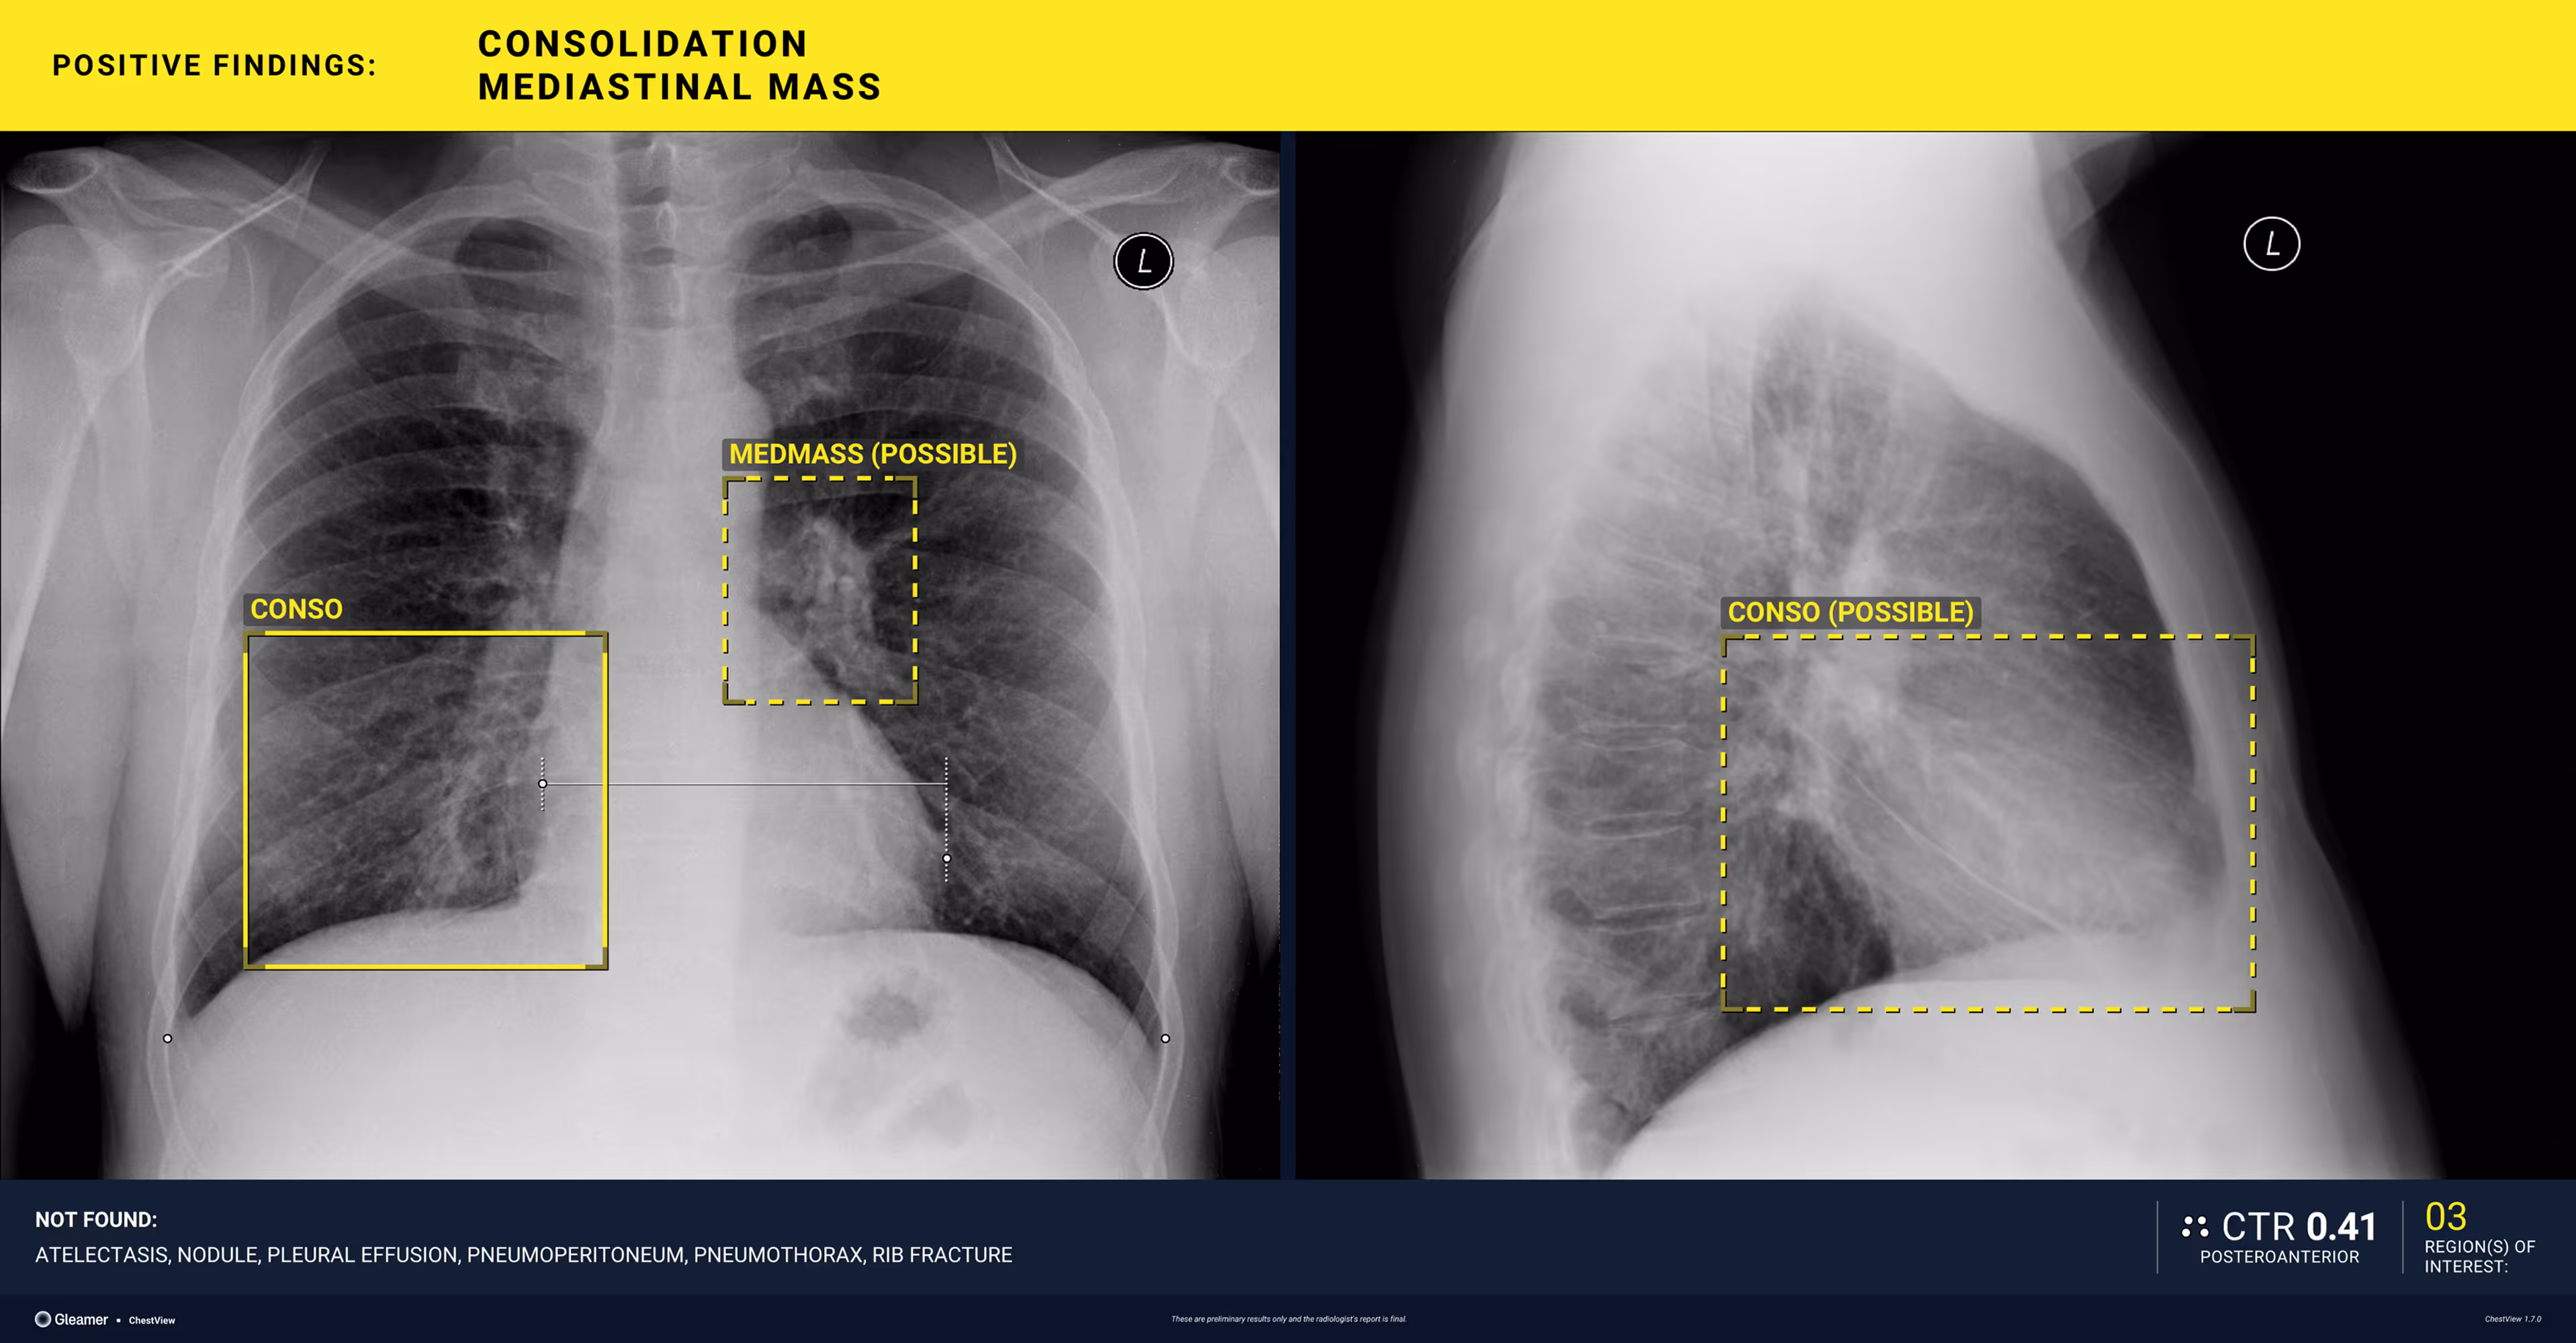

Indication

An 80-year-old male with a previously normal chest X-ray presents for CT evaluation 9 months later, which reveals findings suggestive of lung cancer.

Results

ChestView detected the mediastinal mass on the initial X-ray.